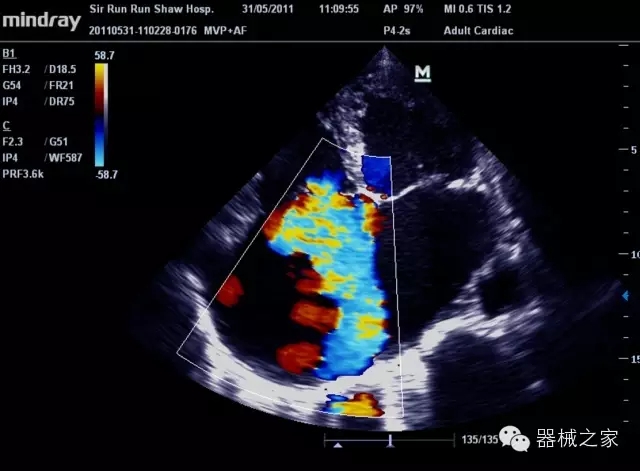

經(jīng)典產(chǎn)品:M7(星鉆)

臨床圖片賞析

產(chǎn)品特點(diǎn)

·優(yōu)秀的圖像效果、強(qiáng)大的功能體驗(yàn)、豐富的探頭選擇、合理的便攜式設(shè)計(jì),全中文顯示及病人管理界面,使得M7在任何場(chǎng)合、任何時(shí)候都能快速響應(yīng)更好的心血管、腹部、婦產(chǎn)、小器官等常規(guī)超聲檢查以及肌骨、神經(jīng)、顱腦、術(shù)中等新興領(lǐng)域的使用需求;

8倍波束并行處理系統(tǒng)

·在便攜式緊湊平臺(tái)上采用更多倍波束并行接收信號(hào)處理模式,無(wú)論二維還是彩色血流圖像狀態(tài)下,擁有更靈敏的回波頻移捕獲能力,大大提高時(shí)間分辨率,尤其使得心血管表現(xiàn)更為突出;